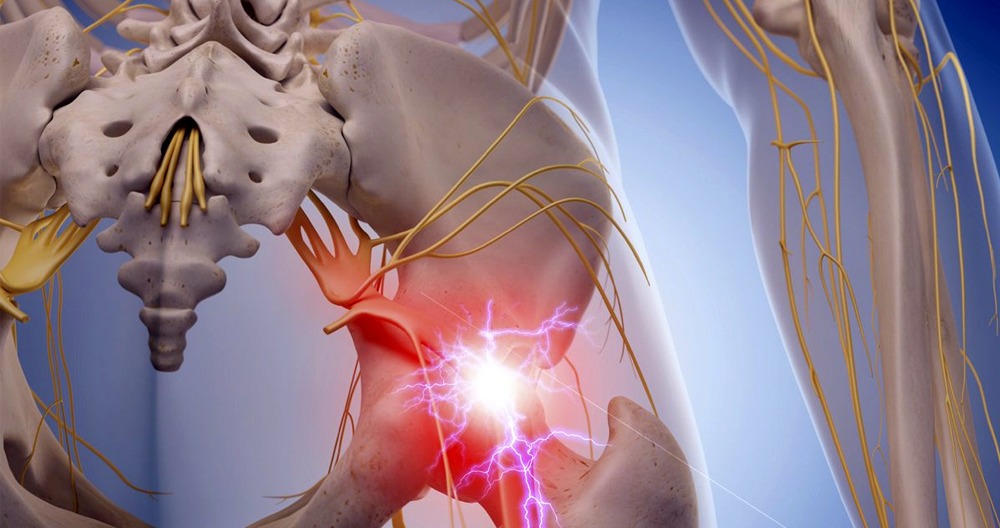

The sciatic nerve is your largest nerve. The sciatic nerve, located in the spine and composed of five nerve roots. This nerve runs down the backs and sides of both legs. It can be affected by dysfunction. It can even reach the feet.

These cushion-like elements, which look like a sponge, protect your vertebrae. They are filled with a gel-like liquid. This fluid presses against the disc’s hard shell, causing pain.

Sometimes, sciatica can be caused by a herniated disc, but it is rarely the reverse. These are the main differences between sciatica and herniated disc. Both conditions can be treated with a variety of treatment options. We can help you get rid of your pain with everything from chiropractic care to physical therapy, acupuncture, medical massaging, and our spine decompression system.